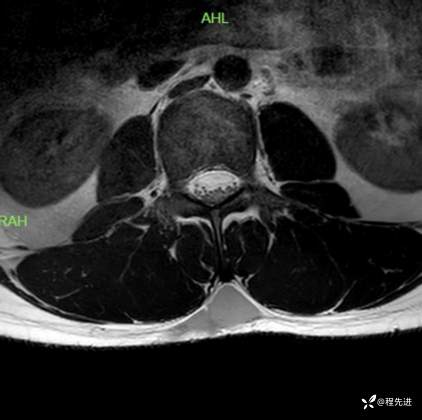

T2横断位:

T1增强压脂横断位: